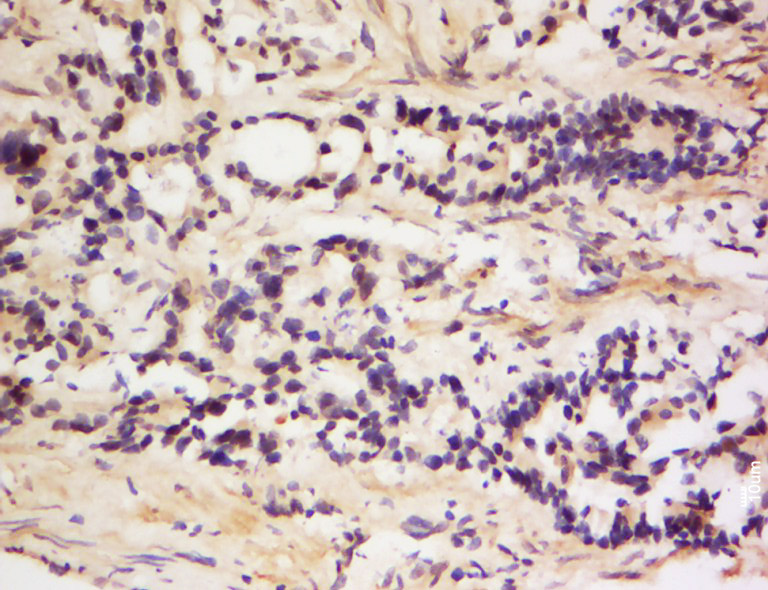

Tissue/cell: Rat testis tissue; 4% Paraformaldehyde-fixed and paraffin-embedded; Antigen retrieval: citrate buffer ( 0.01M, pH 6.0 ), Boiling bathing for 15min; Block endogenous peroxidase by 3% Hydrogen peroxide for 30min; Blocking buffer (normal goat serum,C-0005) at 37℃ for 20 min; Incubation: Anti-Translin Polyclonal Antibody, Unconjugated(bs-16574R) 1:200, overnight at 4°C, followed by conjugation to the secondary antibody(SP-0023) and DAB(C-0010) staining

Tissue/cell: Human colon cancer; 4% Paraformaldehyde-fixed and paraffin-embedded; Antigen retrieval: citrate buffer ( 0.01M, pH 6.0 ), Boiling bathing for 15min; Block endogenous peroxidase by 3% Hydrogen peroxide for 30min; Blocking buffer (normal goat serum,C-0005) at 37℃ for 20 min; Incubation: Anti-Translin Polyclonal Antibody, Unconjugated(bs-16574R) 1:200, overnight at 4°C, followed by conjugation to the secondary antibody(SP-0023) and DAB(C-0010) staining